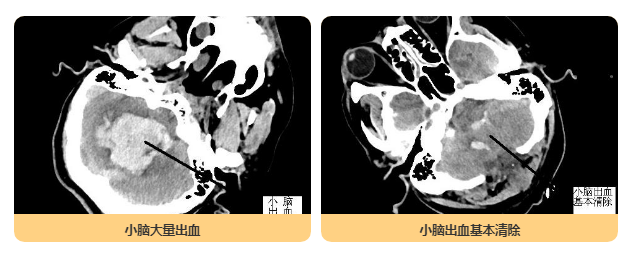

?? ? ? 患者李先生,53歲,被工友發(fā)現(xiàn)躺于宿舍外土坑中,昏迷不醒,由120救護(hù)車緊急送泉州市光前醫(yī)院治療。到院時(shí),李先生已呈昏迷狀態(tài)、呼吸微弱,立即予以緊急氣管插管、呼吸機(jī)輔助呼吸,經(jīng)CT檢查提示右側(cè)小腦出血破入腦室系統(tǒng),腦干(生命中樞)受壓,顱內(nèi)壓力大,需緊急手術(shù)。我院神經(jīng)外科專家立即啟動(dòng)與福醫(yī)大附二院神經(jīng)外科專科聯(lián)盟機(jī)制,聯(lián)系當(dāng)值專家研討患者病情,在其指導(dǎo)下緊急予以止血、脫水減輕顱內(nèi)壓,暫時(shí)穩(wěn)定患者病情。在取得患者家屬同意后,福醫(yī)大附二院值班專家立即從泉州出發(fā),我院同時(shí)完善各項(xiàng)檢查、備血、剃頭等術(shù)前準(zhǔn)備工作,確保專家到院第一時(shí)間即可開展手術(shù)。

? ? ? 經(jīng)我院專家與福醫(yī)大附二院專家攜手合作,患者術(shù)后腦組織壓力減低,腦血管搏動(dòng)有力,生命體征平穩(wěn),轉(zhuǎn)入ICU作后續(xù)治療。

<<<< 手術(shù)前后對(duì)比